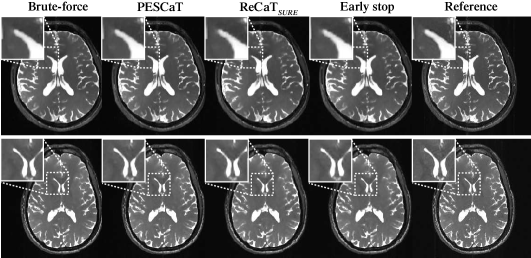

Following these basic demonstrations, PESCaT was performed on bSSFP acquisitions of a simulated brain phantom. Representative reconstructions and error maps for PESCaT and ReCaTSURE with R=6 are shown in Fig. 3. PESCaT yields reduced error across the FOV compared to ReCaTSURE. This improvement with PESCaT becomes further noticeable when ReCaTSURE is stopped early to match its reconstruction time to PESCaT. Quantitative assessments of image quality at R=2, 4, and 6 are listed in Table I. Among all techniques tested, PESCaT achieves the most similar performance to the time-consuming brute-force reconstruction. On average, PESCaT improves PSNR by dB over ReCaTSURE and by dB over ReCaTSURE with early stop (meanstd. across five cross-sections, average of R=2, 4, 6). Note that the proposed method attains near-optimal performance while enabling improved computational efficiency. The average reconstruction time per slice is s for ReCaTSURE and only s for PESCaT, resulting in a 4-fold gain in efficiency for the phantom dataset.

Next, PESCaT was demonstrated for in vivo bSSFP, T1-weighted, and ToF imaging of the brain. Representative reconstructions with R=6 for bSSFP and R=4 for T1-weighted and ToF acquisitions are displayed in Figs. 4, 5, and 6. Representative reconstructions of individual phase cycles in the bSSFP dataset, and of cross-sections in the ToF dataset are shown in Supp. Fig. 11. Overall, PESCaT and ReCaTSURE reconstructions perform similar to the brute-force optimized reconstructions. Yet, PESCaT yields slightly lower levels of residual aliasing in comparison to ReCaTSURE, and this difference is particularly noticeable for visualization of small vessels in ToF images (Fig. 6). The improvement in reconstruction quality with PESCaT is more prominent when ReCaTSURE is stopped early to match its reconstruction time to PESCaT.